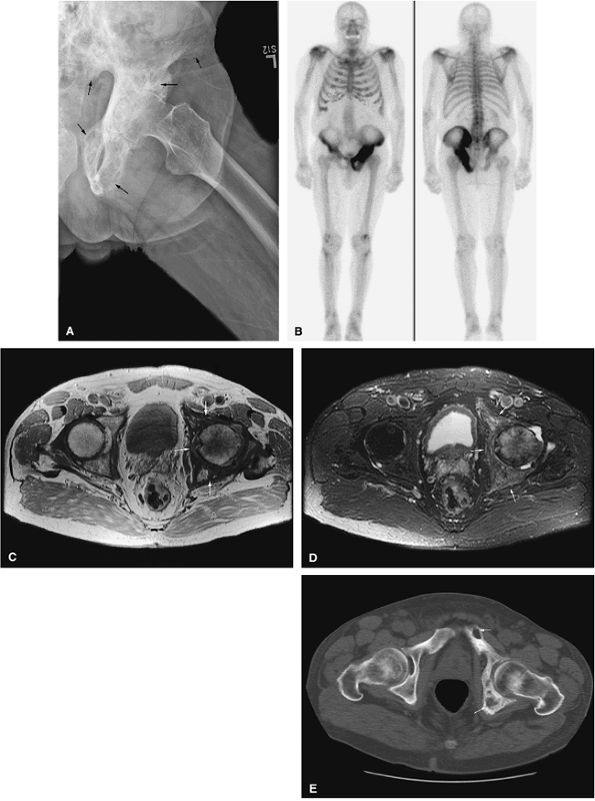

FIGURE 13.36 ● (A) An anteroposterior radiograph of the pelvis is negative for lymphomatous involvement. (B) On a T1-weighted coronal image of the pelvis, the proximal femurs and lower lumbar spine (arrows) display nonspecific low signal intensity. The fatty marrow of the epiphysis and greater trochanter is spared. (C) On a coronal STIR image, there is high-signal-intensity patchy nodularity of lymphomatous marrow involvement in the pelvis, proximal femurs, and lumbar spine (arrows). The spared yellow marrow of the greater trochanter and femoral epiphysis appears black.